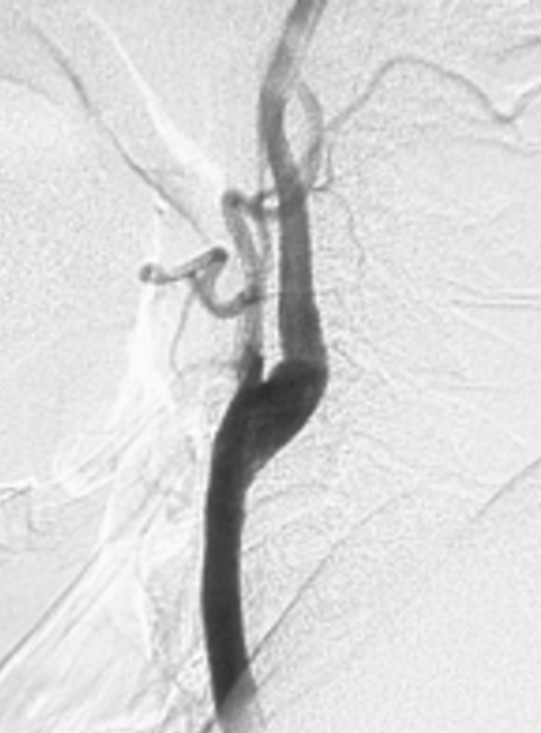

図1:左中等度片麻痺、左同名半盲で発症した脳梗塞症例(74歳男性)の手術前DSA右総頸動脈撮影側面像を提示いたします。右内頸動脈起始部に71%の重度狭窄が見られ、CEAの手術適応があると考えました。(狭窄率の算出法NASCET法= 内頸動脈狭窄部の血管最小径÷狭窄部遠位部の血管径)図2:図1症例の術後DSA右総頸動脈撮影側面像。CEAにより100%以上の血管拡張が得られました。

図2